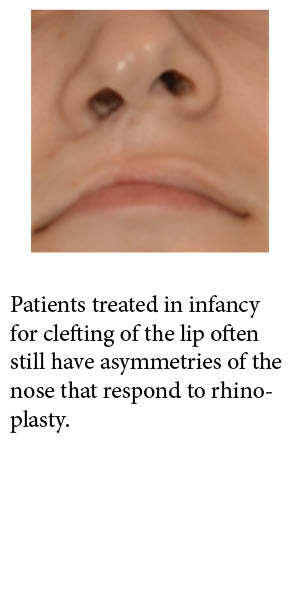

Cleft Lip and Palate

- Patients with cleft lip and palate undergo several surgeries throughout life

- Many patients may still be unhappy with the appearance of their upper lip and may benefit from lip reconstruction or fat grafting.

- Patients may also have persistent nasal disfigurement and nasal airway obstruction that is often responsive to rhinoplasty.

- Patients also may develop teeth misalignment (malocclusion) which can cause facial imbalance, cavities, gum disease and pain in the face or just in-front of the ear (TMJ pain). Facial imbalance can result in poor self-esteem and anxiety around the overall appearance of the face.